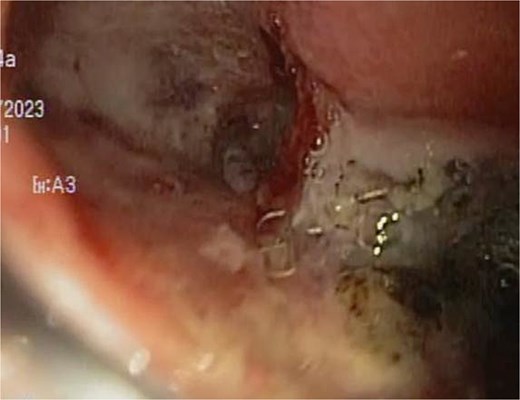

At the last endoscopy 30 days later, 100% granulation tissue was observed with no evidence of a fistulous orifice (Fig. 3). A leak test by fluoroscopy showed no leakage, allowing the initiation of a liquid diet for 15 days, progressing to a normal diet after one month. Follow-up endoscopy showed no pathological findings.

After follow-ups and sponge replacements, the closure of the fistulous defect can be observed.